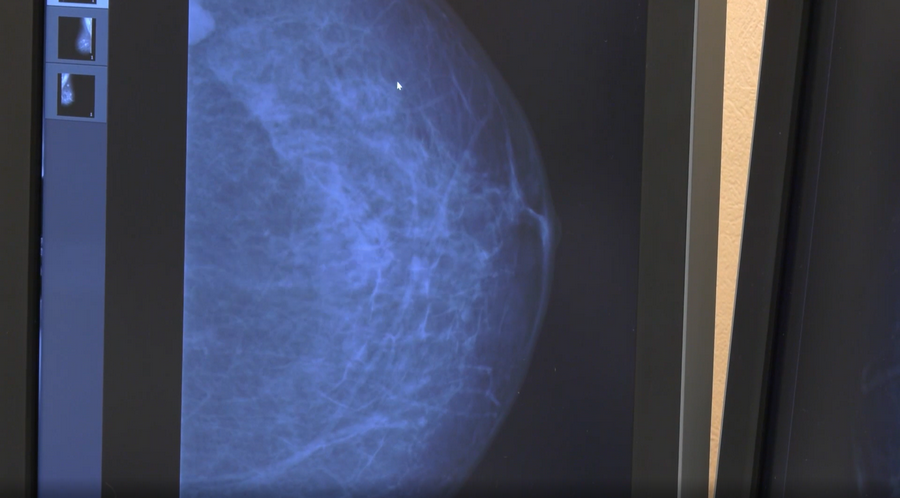

Снимок молочных желез здесь делают в нескольких проекциях, рассказывает врач-рентгенолог Ирина Главатских.

«Если в железах есть новообразования, то мы можем делать прицельные снимки или томосинтез», — уточняет Ирина и добавляет: –

«Мы обязательно указываем, если видим кальциноз стенок сосудов в молочных железах. Это сигнал для кардиолога, что нужно обследоваться. У молодых такое тоже встречается».

«Мы стали чаще видеть такие большие образования. Если раньше они были до сантиметра, то сейчас рак стал более быстро прогрессирующим», — показывает снимки одной из пациенток «Белой розы» врач. Даже неопытным взглядом на рентгене легко найти чужеродное белое пятно.

«В прошлом году к нам приходила женщина, у которой все было чисто и хорошо, а в этом году мы видим образования и в сантиметр и даже больше. Если есть такие показатели, мы рекомендуем обследоваться дважды в год», — сообщает Ирина.

Люди умирают не от рака, поясняет специалист, а от его последствий, от метастазов, и чем раньше удастся обнаружить недуг, тем лучше. «Если он маленький, мы его убираем, и женщина живёт дальше», — подчеркивает Главатских.